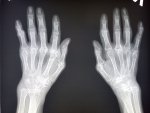

Здравствуй двачик, на прошлой неделе вышел из отпуска и уже дергается глазик, вчера сидел на работке пока поликлинику не закрыли и не все доделал. Не могу перестать кричать внутри головы! Потому мы с вами будем сегодня играть в доктора! Я буду вам показывать фоточки а вы угадывать пиздецомы! Што шпогнали! Найдите поломку!